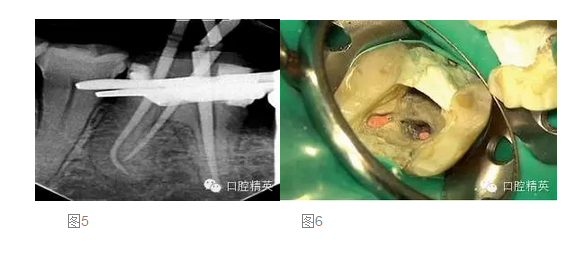

在第二次就診時,我們再次進(jìn)行抗菌的根管沖洗,然后使用消毒的紙尖擦干根管。將牙膠尖置于根管內(nèi),拍攝主尖片(圖 5)。根充糊劑為AHPlus(DENTSPLY DeTrey)。根管充填過程中,使用System B及連續(xù)波加壓技術(shù)對根尖4mm進(jìn)行根管充填,回填過程使用Obtura III Max 的熱塑牙膠(Obtura Spartan)。

在根管充填過程中,要非常小心不要將根充糊劑壓入根管側(cè)穿的部位。對近中舌根的回填置于穿孔的根尖方向(圖 6)。根管充填后,使用MTA 輸送器(同樣也是DENTSPLY Maillefer 公司)對側(cè)穿部位進(jìn)行MTA修補(bǔ),封閉穿孔的部位。正如轉(zhuǎn)診醫(yī)生所要求的,遠(yuǎn)中根管內(nèi)為預(yù)留樁的空間,轉(zhuǎn)診醫(yī)生打算自己進(jìn)行樁道預(yù)備,以放置能夠放射顯影的樹脂樁(圖 7)。使用Cavil G(3MESPE公司)作為冠部的暫封材料。最后叮囑患者復(fù)診以最終修復(fù)患牙,同時6個月后進(jìn)行復(fù)查。